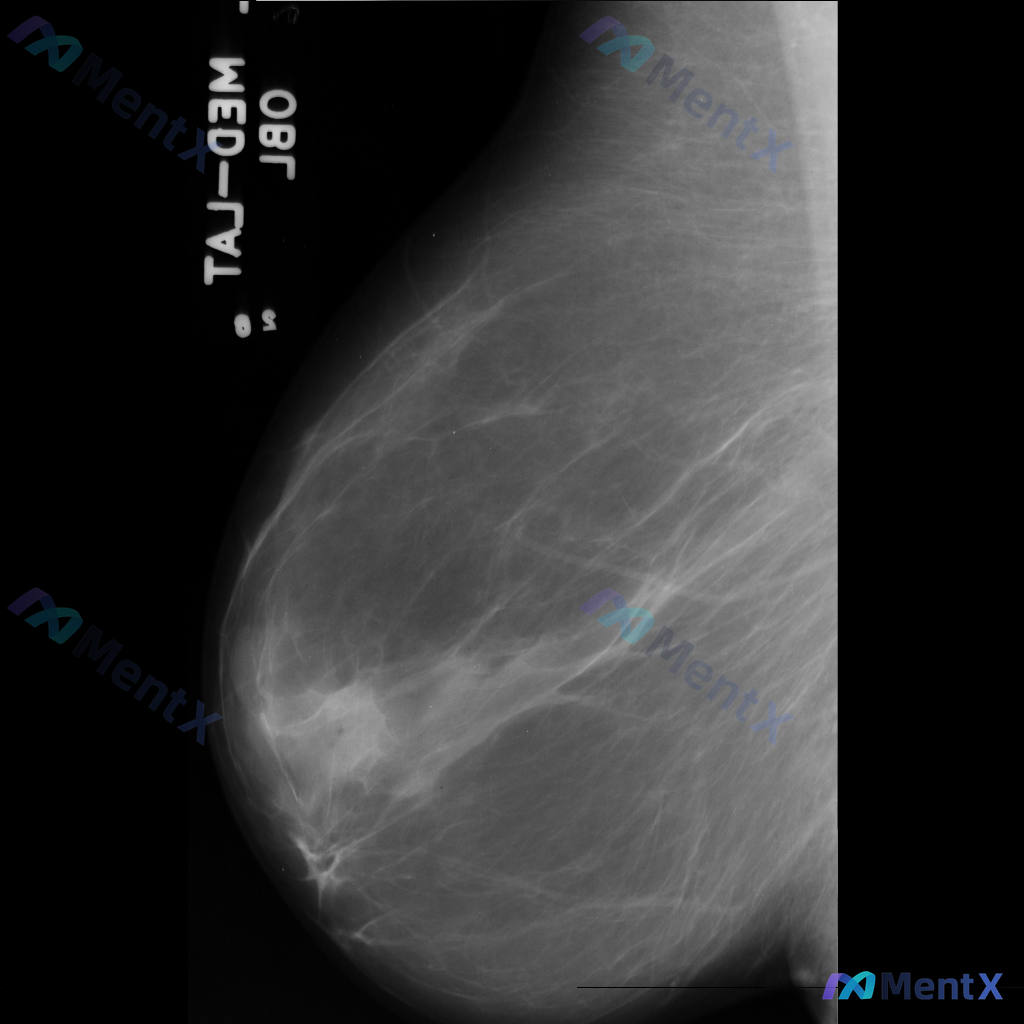

整理到一份乳腺钼靶影像资料,主要表现如下: - 乳腺中后部可见局灶性结构扭曲 - 无明确的肿块核心 - 周围腺体和脂肪界面被不规则牵拉 目前暂不提供既往影像对比和详细病史(手术史、外伤史、炎症史等)。 这种表现大家会先怎么判断?更倾向于往哪种方向考虑?

整理到一份乳腺影像的分析资料,想请大家一起讨论看看。 基本信息: - 影像类型:左侧乳腺钼靶内外斜位(MLO) 影像主要表现: 1. 左侧乳腺中上部及外侧可见局灶性结构扭曲 2. 乳腺腺体组织以纤维腺体为主,密度较高,为不均匀致密型(ACR BI-RADS C型) 3. 腺体可见多发斑片状、结节状高...